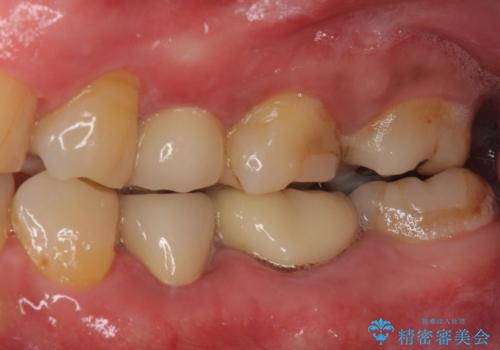

詰め物の外れてしまった奥歯 部分矯正で歯列を整えてから補綴治療